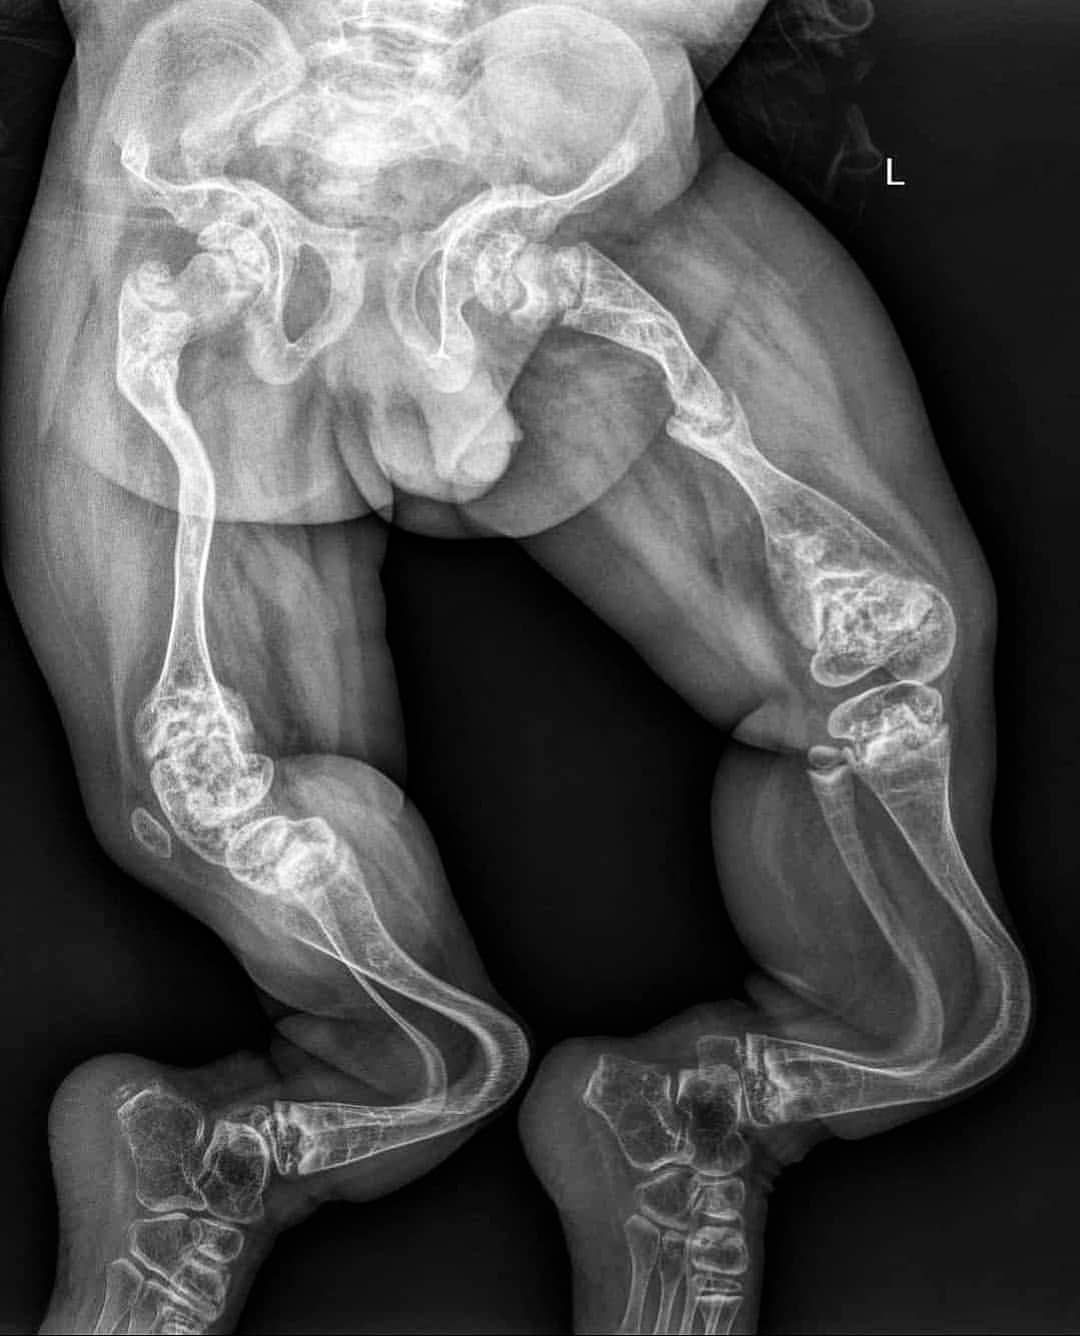

X-ray of a child with a disease known as osteogenesis imperfecta type III with progressive deformities in the lower extremities, together with severe osteoporosis, fragile bones, and coxa vara. Left femoral shaft fracture is seen with pseudarthrosis formation. Osteogenesis imperfecta (OI) is an inherited (genetic) bone disorder that is present at birth. It is also known as brittle bone disease. A child born with OI may have soft bones that break (fracture) easily, bones that are not formed normally, and other problems. Signs and symptoms may range from mild to severe.